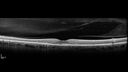

51 year old female on with trouble driving at night for a year. No eye examination for several years. 2009 (11 years ago) Plaquenil 300 then up to 400 a few years ago now down to 300 - 5'2" 135 lbs

VA 20/20 OD, 20/25 OS